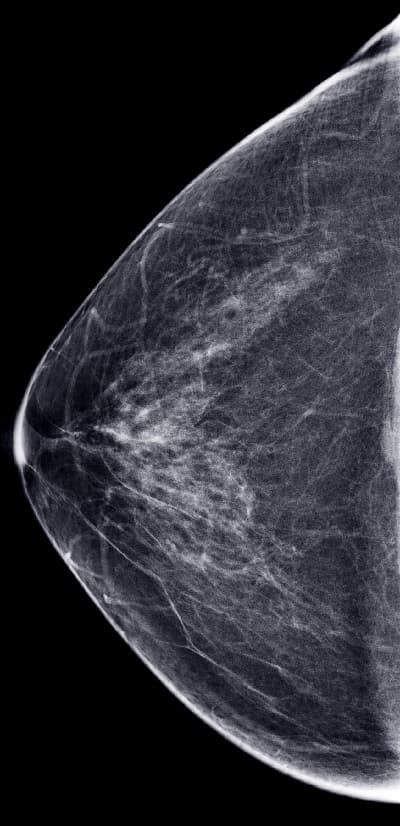

My mammograms with breast implants – the implant is seen as the large white half-dome, and the breast tissue is visualized on top and around the implant

In addition to the standard views, additional implant displacement (ID) views – I call these the “horizon views” (see below) are taken when you have breast implants. The breast tissue is displaced forward off the implant, and is visualized lying overtop of the implant, as seen in my own mammograms, above. The implant is pushed back against the chest wall and the breast is pulled forward over it and then compressed. This allows better imaging of the front part of each breast so the doctor can get a better look at the breast tissue.